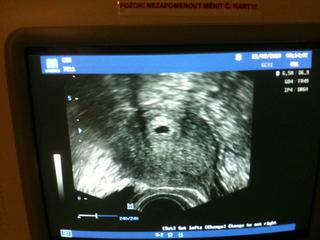

tak vsetko je tak ako ma byt 😉, srdiecko uz bilo 😉, mame malu fazulku 😉. a podla velkosti som 5+2. mali zo mna v care radost, ze som ich posetila, hned zrana 😉. dokonca ma vzali bz objednania prvu. bola som u jarosovej.

pridavam aj foto, neni tam nic vidiet, iba taka mala fazulka 😉, tak to je nas dorbcek 😉

inak schodzka zacala tak, ze Jarosova sa kukla do karty a zacala, tak vy si dnes idete pre injekciu. ja na to, ze nie tak uplne, ze som si spravila tehu curaci testik a som tehotna. tak hned zacala ze kolky den a tak, ze sa na mna hned kukne. mala by som byt 6+2. a ze uz nieco by malo byt vidiet. tak na mna kukla na ultrazvuku a hovori ze som 5+2 a ze srdiecko bije tak ako ma, ze prcek je v delohe. takze je vsetko na najlepsej ceste. za 15 dni idem ku nej na kontrolu a potom mi spravia nejaky kompletny screening. joj mam radost 😉

@len s tym srdieckom si mala pravdu 😉. ja som nejak poplietla to co mi dr povedala. este srdiecko tam neni vidiet, iba je tam nejaky vacok a v tom vacku bude srdiecko. aspon tak to dnes citala v sprave od minula. ja som to riadne splietla. to bol sok, slzi stastia a do toho niekto nieco hovoril 😉. ospravedlnujem sa za metenie.